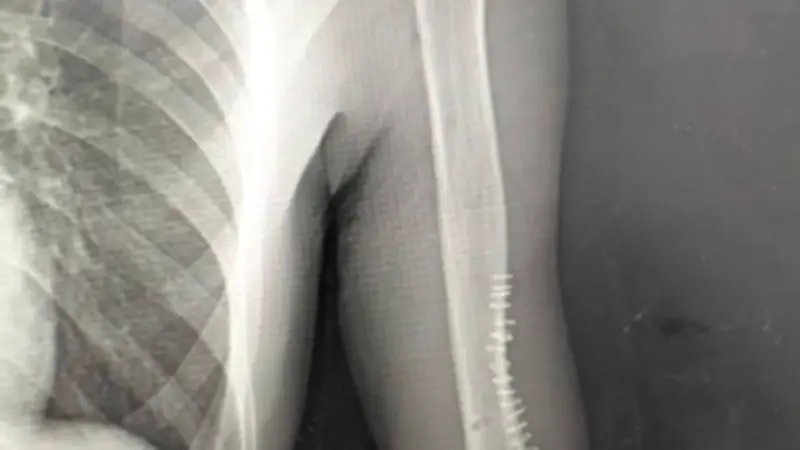

جاءت العملية تحت إشراف الدكتورة رشا عادل شفيق مدير عام إدارة الطب العلاجي، والدكتور أحمد جلال مدير إدارة المستشفيات، والدكتور أحمد عبد الغني مدير مستشفى الغردقة العام، وبقيادة الدكتور مجدي عزيز رئيس قسم واستشاري جراحة العظام. تم التعامل مع حالة مريض يعاني من تيبس وتشوه بمفصل المرفق الأيسر نتيجة كسر قديم بعظمة العضد تم تثبيته سابقًا باستخدام شريحة ومسامير.

أظهرت الفحوصات وجود الشريحة في موضع حرج داخل مجرى المفصل بالقرب من العصب الكعبري المسؤول عن حركة الرسغ والأصابع، مما شكّل خطورة كبيرة بسبب وجود التصاقات حول العصب واحتمالية تعرضه للتلف، وهو ما قد يؤدي إلى ضعف أو شلل باليد.

شمل التدخل الجراحي إجراء تسليك دقيق للعصب الكعبري ورفع الشريحة مع الحفاظ الكامل على سلامة العصب ووظائفه، إلى جانب تحريك المفصل تحت التخدير في حدود الأمان وفقًا لحالة الضفيرة العصبية والدورة الدموية. أُجريت العملية بواسطة فريق قسم جراحة العظام الذي ضم الدكتور مينا رفعت أخصائي جراحة العظام، والدكتور محسن، والدكتور هشام، أطباء مقيمين، بينما تولى التخدير الدكتور محمود، بمساعدة الممرضة أسماء.